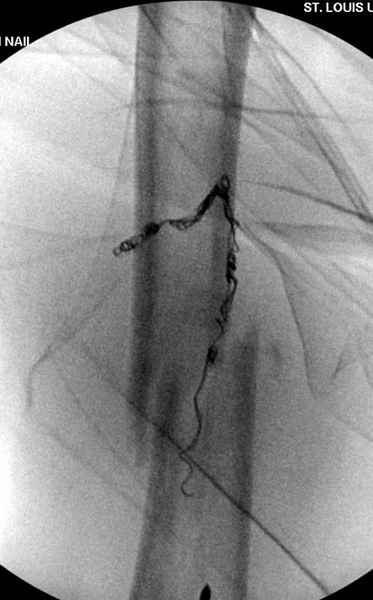

Для предупреждения кровотечения во время рассверливания, за день до операции провели эмболизацию сосудов питающий метастаз. http://radiology.rsnajnls.org/cgi/reprint/150/3/673.pdf (7-11, 12-15-16)

С минимальным рассверливанием и ретроградным методом провели остеосинтез бедра 12 мм гвоздем. (17-20)